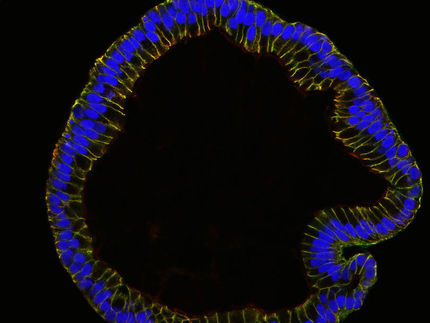

© Insel Gruppe, Grafik: A. Lämmle, mwy

Schematische Darstellung des Harnstoffzyklus. Beim Abbau von Eiweissen in der Leber entsteht giftiger Ammoniak. Dieser wird im Harnstoffzykluns abgebaut. Die häufigste Störung bewirkt, dass kein OTC (Ornithintranscarbamylase) gebildet werden kann. Fehlt OTC, reichert sich Ammoniak an, es kommt zu Vergiftungen. Das Forschungsteam hat den künstlichen Stammzellen das Transportprotein Aquaporin 9 (unten links) eingefügt. Damit funktionieren die künstlichen Leberzellen wie die Leberzellen und können z.B. in Medikamententests gegen OTC-Defekt eingesetzt werden.